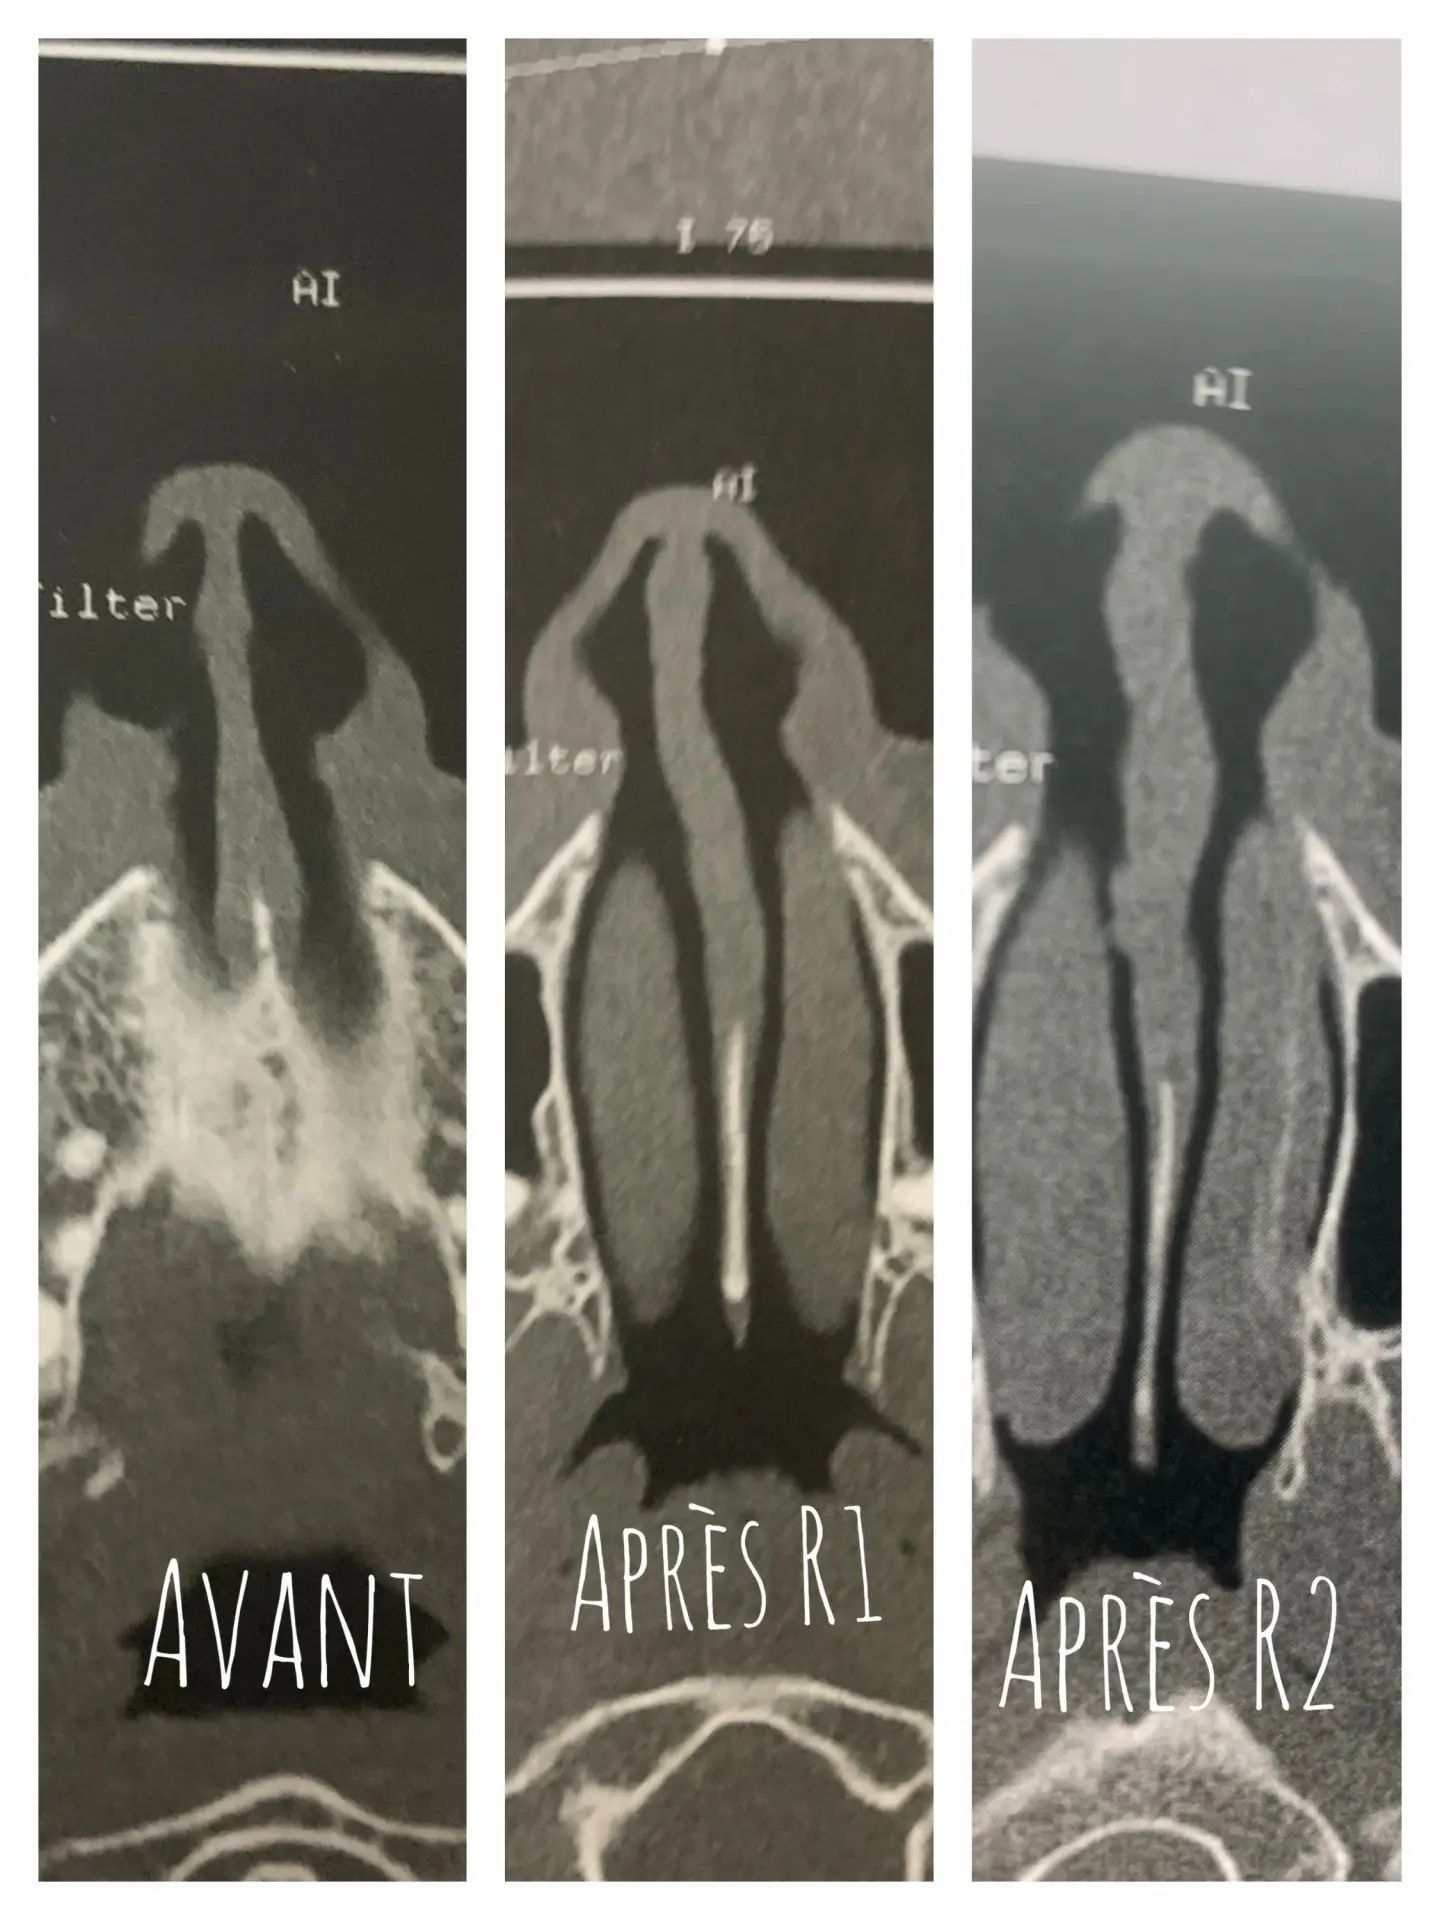

Source: apollopanrl.pages.dev Persistance de la déviation après 2 rhinoseptoplasties Septoplastie (opération de la cloison , Les éperons osseux nasaux se développent à la suite d'un traumatisme causé au nez par un coup Elle favorise la survenue de sinusites, rhinites et ronflements.